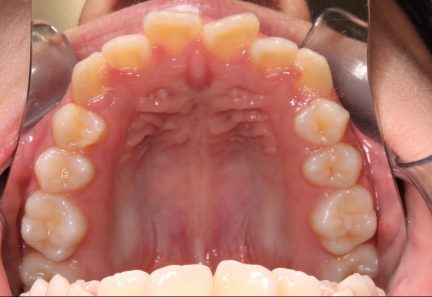

État initial

État final

- Le recouvrement a été corrigé à l'aide de taquets d'égression optimisés

- L'espace nécessaire a été créé pour que les canines hautes fassent éruption

- La rétraction des dents inférieures a été réalisée à l'aide d'élastiques de classe III, pour corriger le surplomb optimal et obtenir des canines et molaires de classe I.